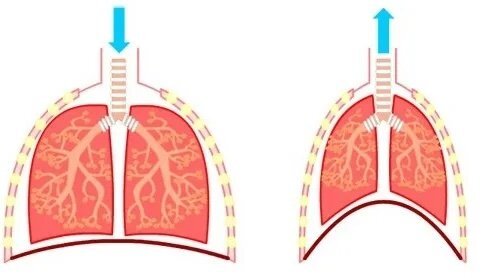

Your diaphragm is a muscle below your lungs, represented here with a dark red line.

Think of your diaphragm as an upside-down-bowl that turns into a plate as it contracts, sucking air into the lungs via the vacuum it creates as it pushes itself flat. Since this muscle pushes down on the top of your belly as air enters your lungs, your belly sticks out. After inhaling, you allow your diaphragm to relax back into its upside-down bowl and naturally exhale. Belly breathing is not about pushing your belly out. It’s about allowing your diaphragm to contract (inhale, think of the diaphragm as flat plate pushing down) then relax (exhale, the diaphragm returns to its upside-down bowl state).